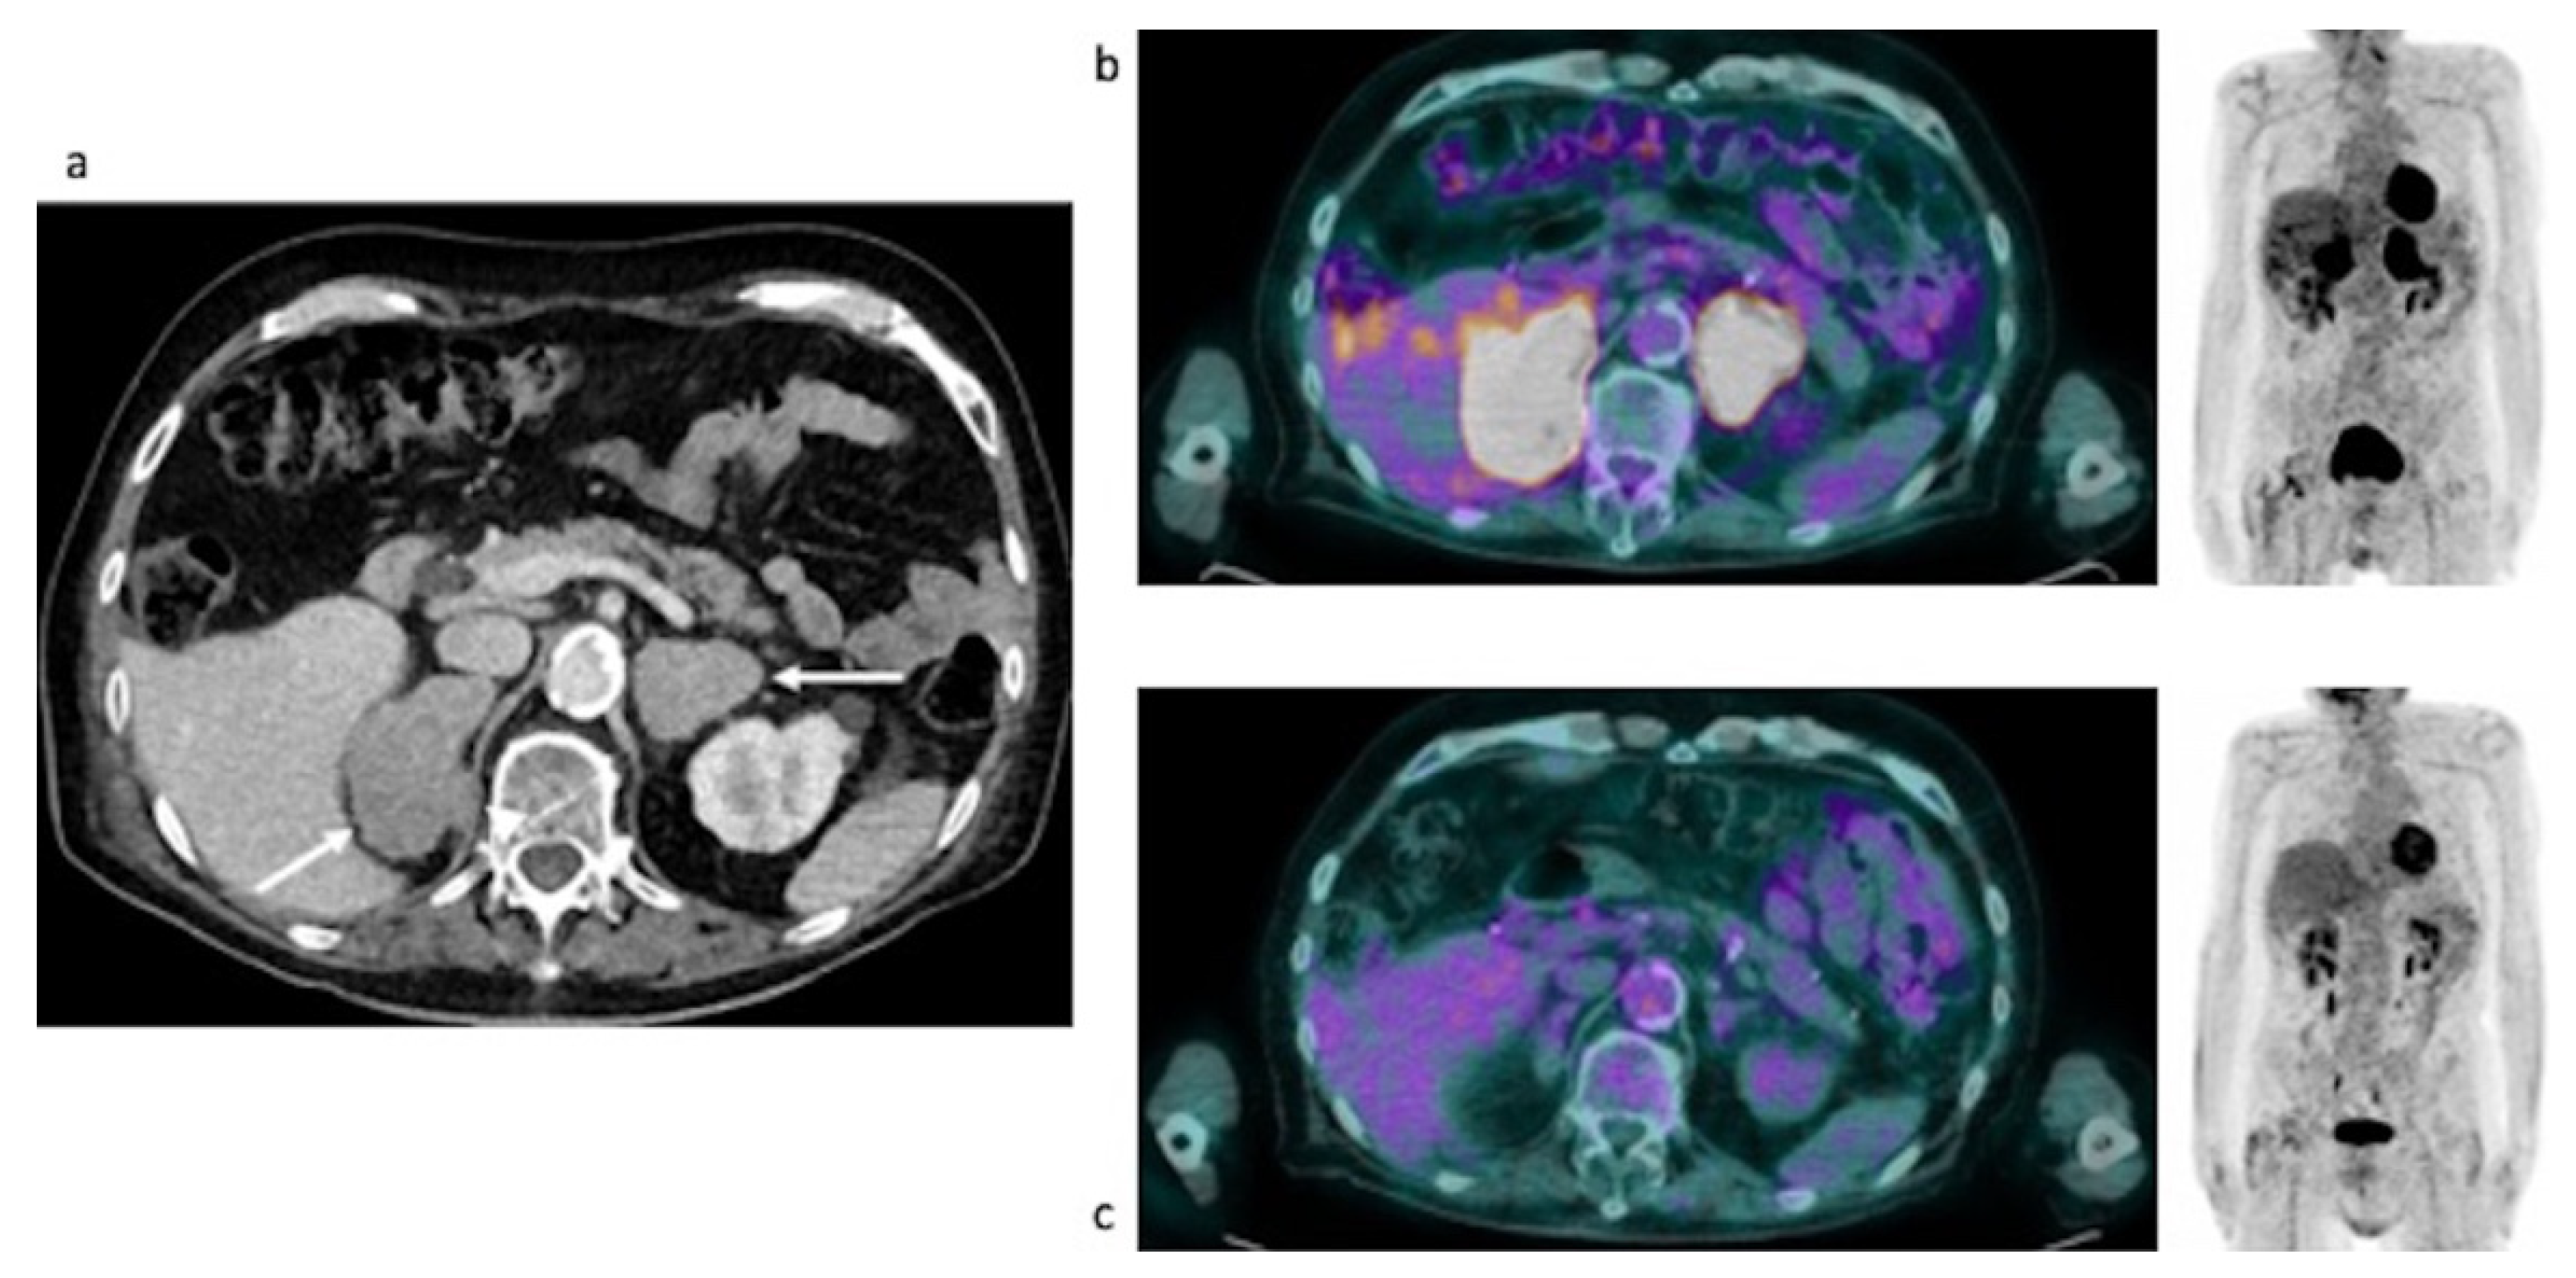

Case #4